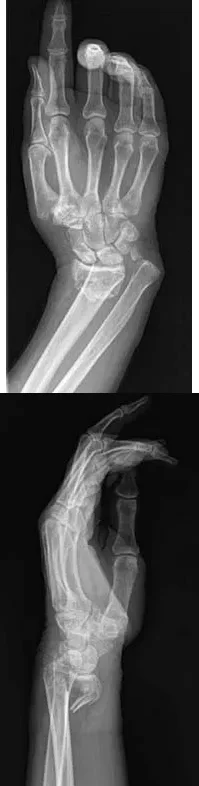

Question 7

A 64-year-old woman sustains the wrist injury shown in the radiographs. The injury is a volar displaced intra-articular distal radius fracture. When utilizing a volar buttress plate for this specific fracture pattern, what is the primary biomechanical function of the plate?

Explanation

Correct Answer: C

The radiographs show a volar Barton's fracture (volar displaced intra-articular fracture of the distal radius). The primary deforming forces are axial loading and volar shear, which cause the carpus to subluxate volarly with the fracture fragment. A volar buttress plate is applied to physically block (buttress) this volar displacement, neutralizing the axial and shearing forces.

Question 17

A 64-year-old woman sustains the wrist injury shown in the radiographs after a fall on an outstretched hand. The fracture pattern involves a volar displaced intra-articular fragment. What is the primary biomechanical rationale for utilizing a volar buttress plate in the surgical management of this specific injury?

Correct Answer: It neutralizes axial loading forces on the fractured volar fragment.

The radiographs demonstrate a volar Barton's fracture, which is a volar displaced intra-articular fracture-dislocation of the distal radius. The volar carpal ligaments remain attached to the volar fragment, pulling the carpus volarly. A volar buttress plate is biomechanically ideal for this injury because it acts as an anti-glide plate, neutralizing the axial loading and shear forces that drive the fragment proximally and volarly. A dorsal plate would not provide this buttress effect and would make maintaining the reduction difficult.

Question 40

A 64-year-old woman sustains a wrist injury after a fall. Radiographs demonstrate a volar displaced, intra-articular distal radius fracture-dislocation. Which of the following surgical approaches and fixation methods is most appropriate to neutralize the axial loading forces on the fractured fragment?

Correct Answer: B

The radiographs show a volar Barton's fracture (volar displaced intra-articular distal radius fracture-dislocation). The most biomechanically sound treatment is an open reduction through a volar approach and stabilization with a volar buttress plate. The buttress plate effectively neutralizes the axial loading and shear forces that drive the volar fragment proximally. A dorsal plate cannot provide this buttress effect for a volar shear fracture.